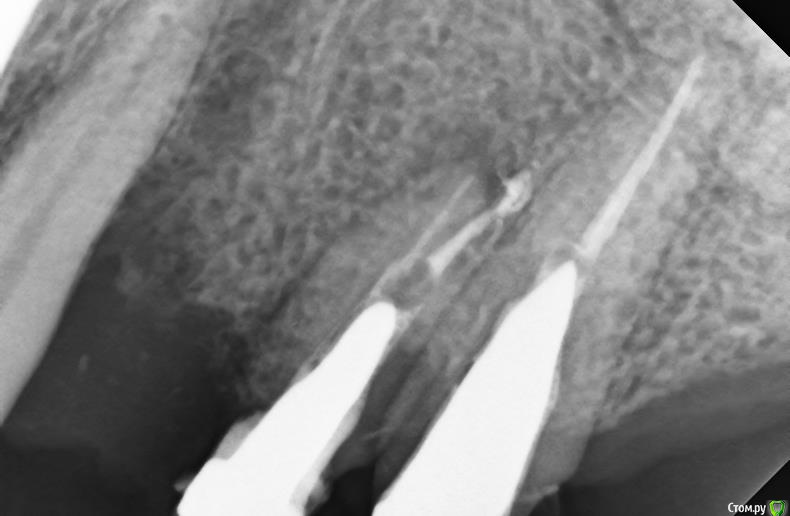

alex_ddd Опубликовано 29 июля, 2016 Автор Поделиться Опубликовано 29 июля, 2016 Ну, вот сегодняшний снимок 24 Ссылка на комментарий

alex_ddd Опубликовано 29 июля, 2016 Автор Поделиться Опубликовано 29 июля, 2016 Попытка 2 Ссылка на комментарий